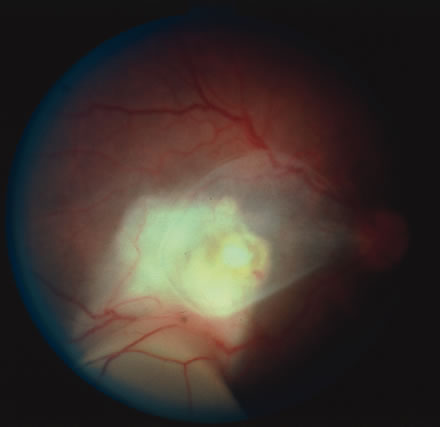

The acute retinal necrosis (ARN) syndrome is most often caused by the herpes zoster virus, although occasionally it may be a result of herpes simplex infection.12 It is typically described in healthy patients although association with immunosuppressed patients has also been described. Granular, nonhemorrhagic areas of retinal necrosis may be observed in the fundus, often rapidly coalescing with resulting blindness often caused by retinal detachment. There is often an associated vasculitis and vitritis. In immunocompromised patients VZV or HSV retinitis may also take the pattern of progressive outer retinal necrosis (PORN) (Fig. 6). PORN differs from ARN in that the former is multifocal, localized to the outer retina, and is less often associated with vasculitis and vitritis.

Fig. 6. Fundus lesions of progressive outer retinal necrosis (PORN). Note the multifocal lesions.